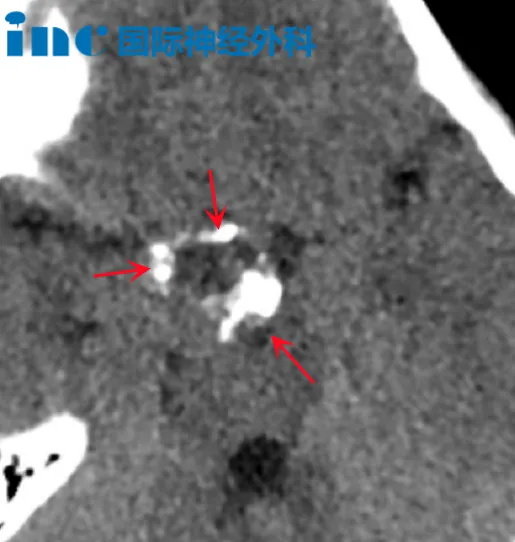

常说病来如山倒,对于部分脑瘤患者来说,更是如雪崩一般的灾难,短短几天的时间,就能剥夺一个人正常生活的能力。51岁的患者吴先生2024年3月20日由于突发的头痛头晕、左眼视力模糊复视、轻微面瘫、血压增高紧急送医。住院治疗后仅过去两天,吴先生出现吞咽困难症状,怀疑脑干-延髓肿瘤占位性病变。病情进展之快让吴先生一家陷入较大的黑暗之中。23日,距离出现症状仅过去3天,吴先生已经无法吞咽进食,只能鼻饲。十万火急之下,吴先生一家发动了身边的全部朋友为吴先生求医。

"咨询巴教授,十万火急!",3月27日在收到吴先生的求救留言后,INC工作人员尽快联系了吴先生,整理好吴先生的病例资料。此时巴教授正在苏州进行疑难脑瘤示范手术,在手术间歇期间还没换下手术服的巴教授,紧急为吴先生进行了远程视频咨询。

此时的吴先生只能鼻饲、状态虚弱、胃管逆流出红色液体。在查看过吴先生的影像资料后,巴教授表示由于弥漫性生长特点、以及恶性的进展速度,这种肿瘤并没有手术意义,目前吴先生需要尽快去所在区域医院医院肿瘤科进行放化疗合并治疗。